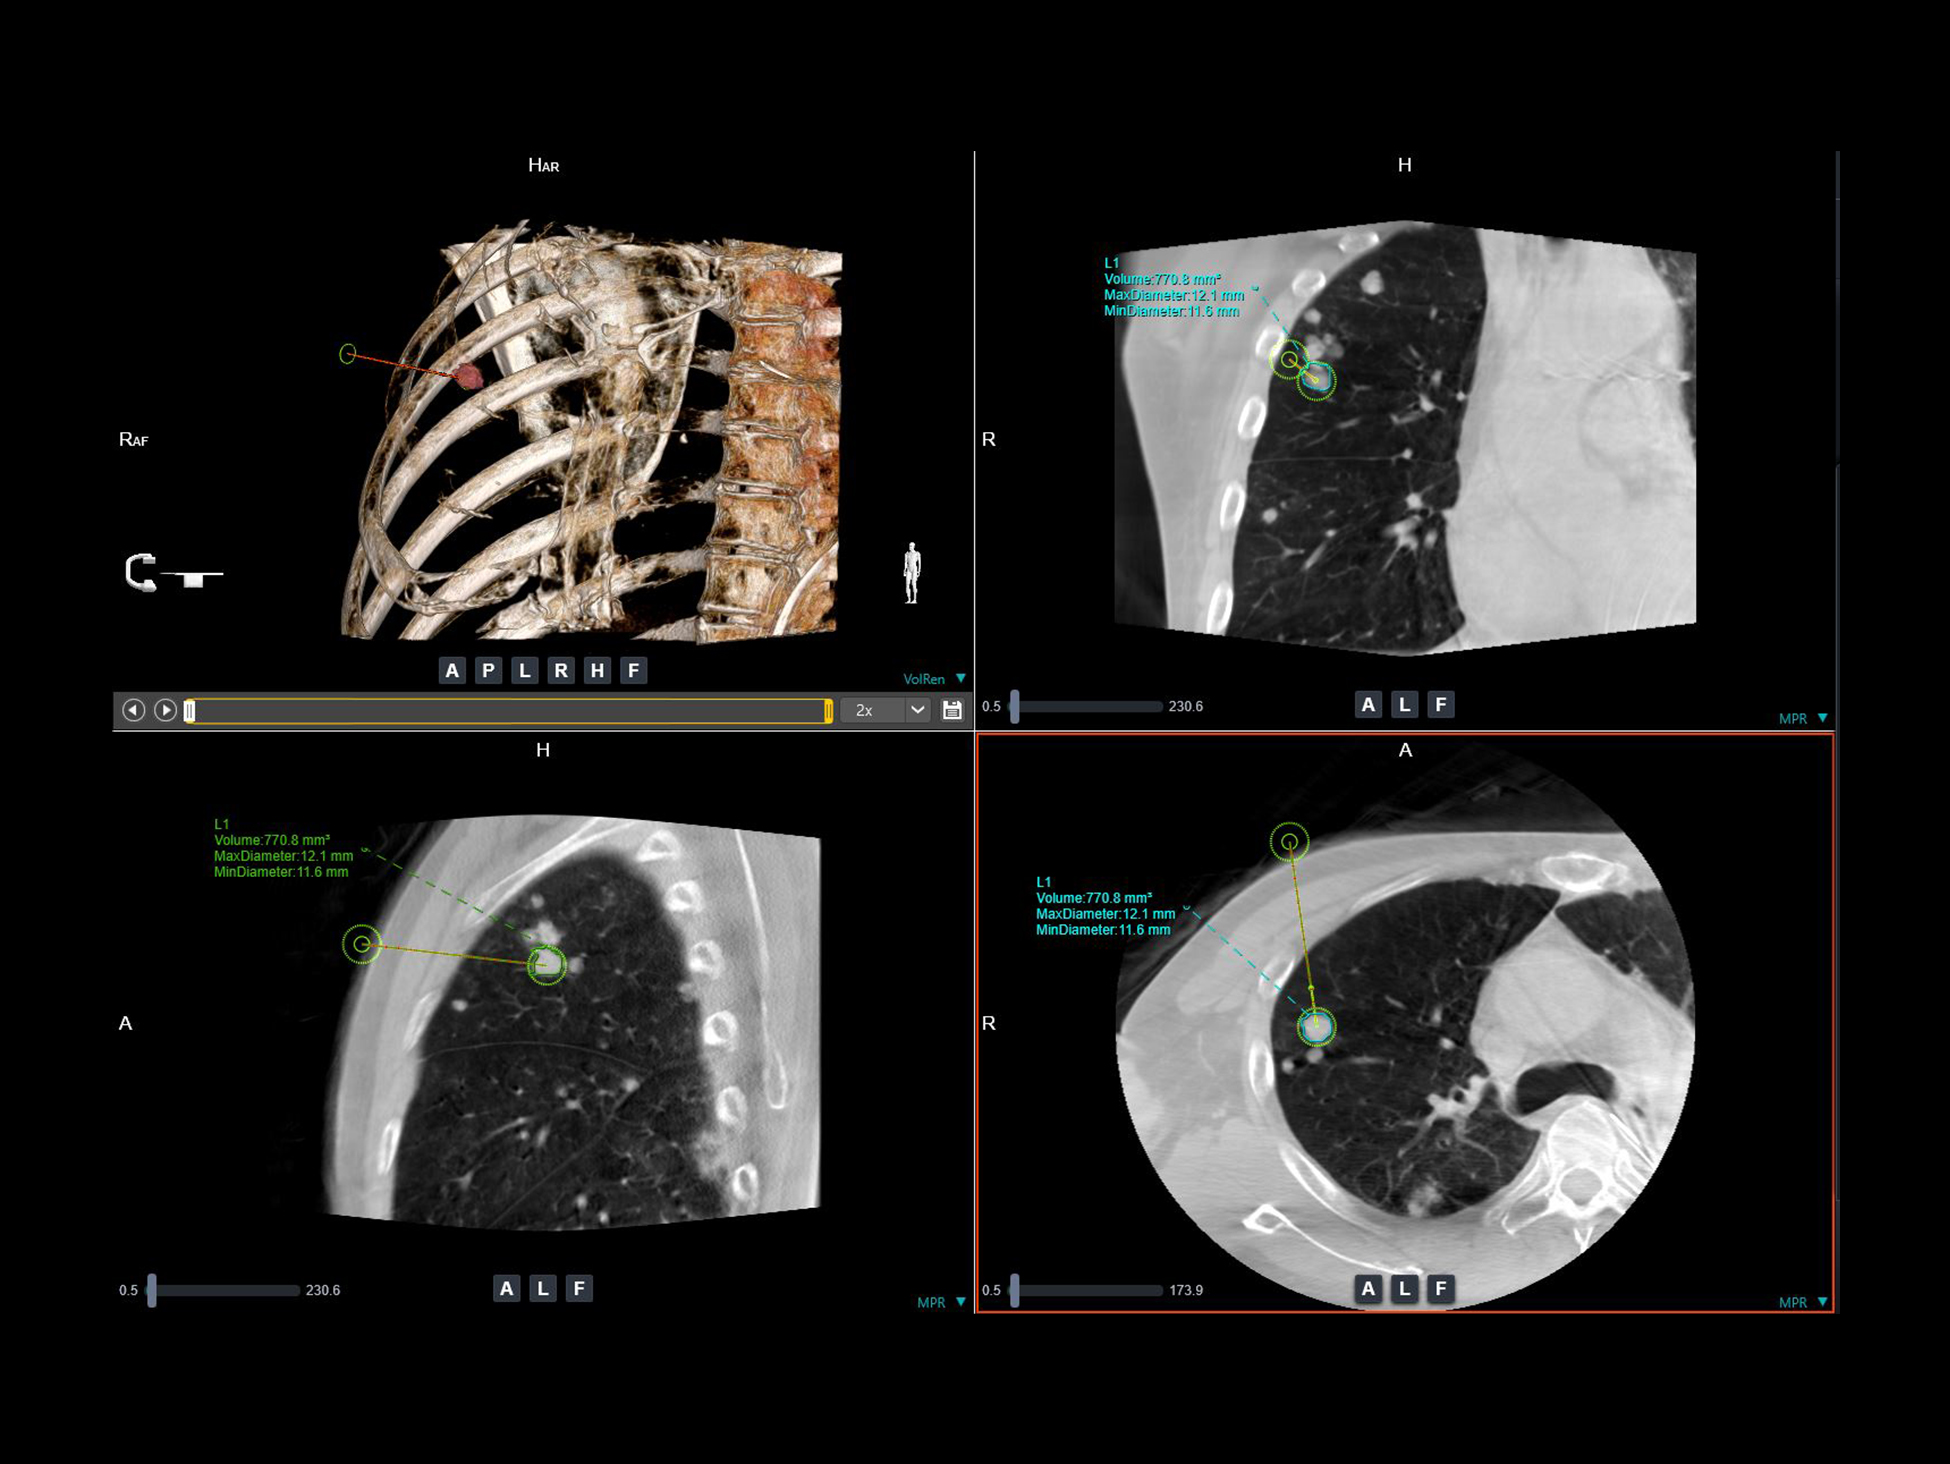

uTarget View*

Sistem de navigație precisă pentru ghidarea acului, care oferă un flux de lucru integrat cu segmentare semi-automată a tumorii, ghidare laser și afișarea în timp real a traiectoriei planificate.